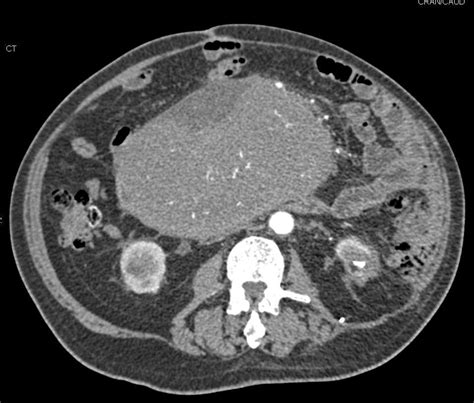

Small Bowel Tumor - Small bowel neoplasms are rare, accounting for 0.5% of all cancers and approximately 3% of all. Your small intestine is part of your. Small intestine cancer happens when malignant (cancer) cells form in your small intestine, or small bowel. The differential diagnosis of small bowel tumors includes many infectious and inflammatory diseases, that all present with focal bowel wall thickening..